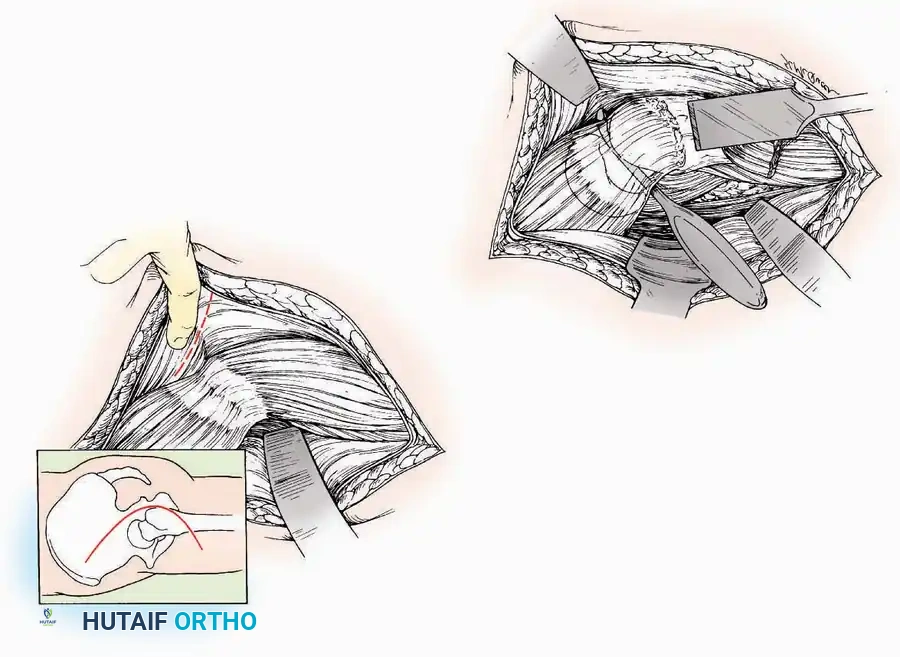

Anterior Approach

Indications: Total ankle arthroplasty (TAA), anterior ankle arthrodesis, and excision of anterior tibial/talar osteophytes (anterior impingement).

Surgical Technique:

* Incision: Make a 10 to 15 cm longitudinal incision over the anterior aspect of the ankle, centered exactly midway between the medial and lateral malleoli.

* Superficial Dissection: Incise the superficial fascia. Identify and protect the superficial peroneal nerve branches laterally and the saphenous nerve medially.

* Internervous Plane: The deep dissection exploits the plane between the Extensor Hallucis Longus (EHL) tendon (innervated by the deep peroneal nerve) and the Extensor Digitorum Longus (EDL) tendons (also innervated by the deep peroneal nerve).

* Neurovascular Bundle: Incise the extensor retinaculum. Carefully identify the anterior tibial artery and the deep peroneal nerve, which typically lie between the EHL and EDL, or directly deep to the EHL. Retract the neurovascular bundle laterally with the EDL, or medially with the EHL, depending on the specific anatomical variant encountered (lateral retraction is most common).

* Capsulotomy: Incise the anterior joint capsule longitudinally. Elevate the capsule subperiosteally from the anterior tibia and the talar neck to expose the entire tibiotalar articulation.